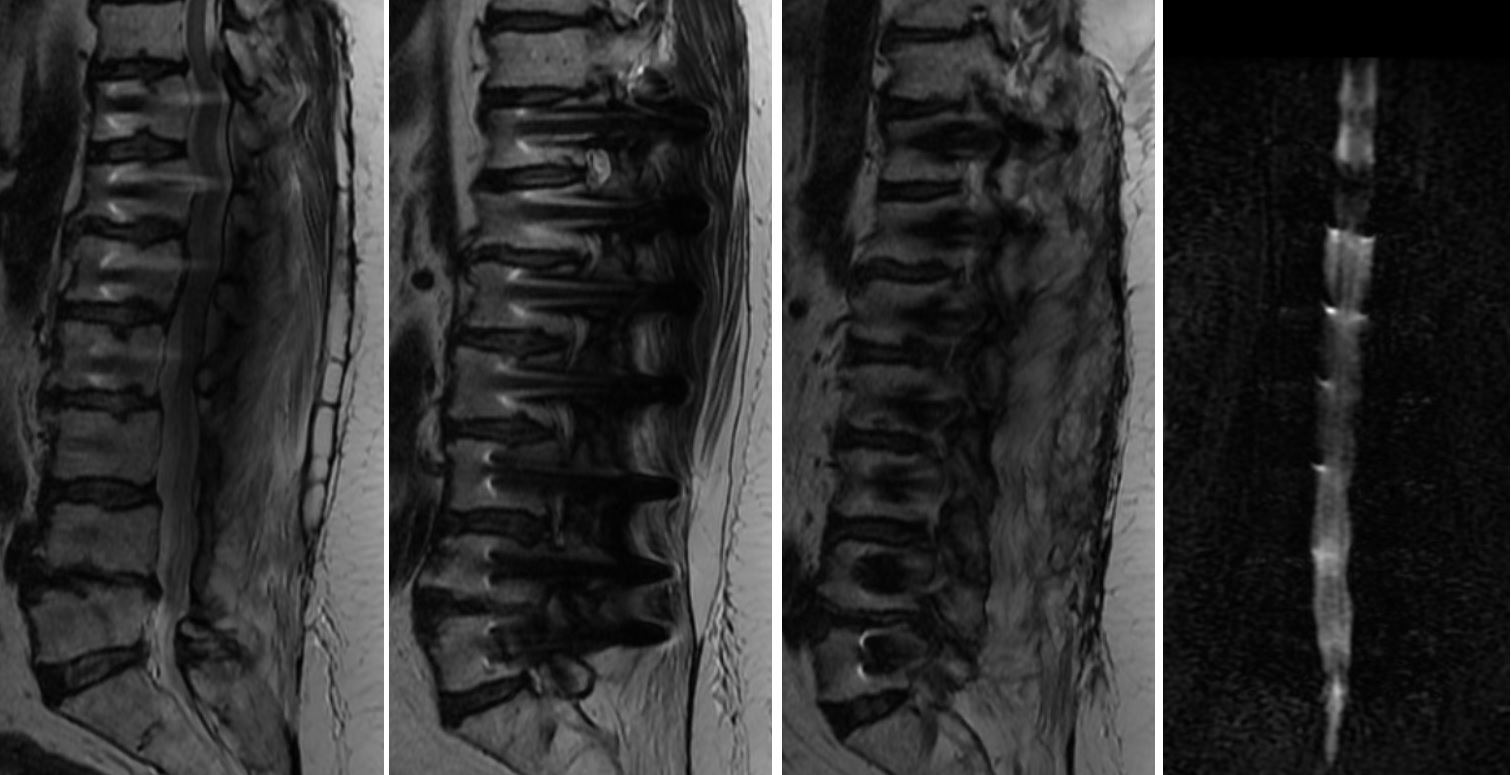

Hastanın beraberinde getirdiği ve bir önceki yıla ait lomber MRG incelemesi aşağıdadır.

2021 Yılı MRG İncelemesi - Lomber Enstrüman Gevşemesi

Resim 1: Bir yıl önce yapılmış olan MRG incelemesinde T11-L5 seviyelerinin stabilize edilmiş olduğu, L2-L4 seviyelerinde laminektomi bulunduğu ve L4-5 seviyesinde kanalda darlık olduğu görüldü. Ayrıca lomber lordozun düzleşmiş olduğu dikkati çekmektedir. MRG kalitesi düşüktür.

Uzun segment (T11-L5) stabilizasyon yapılmış olan hastanın istirahatte bulunan kalça ve bacak ağrıları ve uyuşma yakınmaları spinal kanalda ya da nöral foramenlerde daralmalara bağlı nöral bası düşündürtmektedir (Bacaklardaki kramplar nörojenik kladikasyon tablosunun bir parçası olabilmekle birlikte, tipik siyatalji tablosunun bir parçası değildir, başka sebepler de aramak gerekir).

Hareketle artan bel ağrısı instabilite, alt lomberde implant üzerine basmakla uyandırılan şiddetli ağrı ise implant gevşemesi lehinedir.

Bu hastada olası tanılar komşu segment hastalığı (T11 üstü ve L5 altı seviyelerde hızlanmış dejenerasyona bağlı darlıklar ve/veya instabilite) ve implant gevşemesidir. Stabilize edilmiş L4-5 seviyesinde darlık görülmesi, buna karşın L5-S1 seviyesinin nisbeten korunmuş oluşu L4-5 seviyesinde füzyon oluşmadığı ve implant gevşemesi olabileceği yönünde fikir oluşturmaktadır.